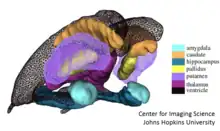

The applications within medical imaging of computational anatomy continued to flourish after two organized meetings at the Institute for Pure and Applied Mathematics conferences[52][53] at University of California, Los Angeles. Computational anatomy has been useful in creating accurate models of the atrophy of the human brain at the morphome scale, as well as Cardiac templates,[54] as well as in modeling biological systems.[55] Since the late 1990s, computational anatomy has become an important part of developing emerging technologies for the field of medical imaging. Digital atlases are a fundamental part of modern Medical-school education[56][57] and in neuroimaging research at the morphome scale.[58][59] Atlas based methods and virtual textbooks[60] which accommodate variations as in deformable templates are at the center of many neuro-image analysis platforms including Freesurfer,[61] FSL,[62] MRIStudio,[63] SPM.[64] Diffeomorphic registration,[18] introduced in the 1990s, is now an important player with existing codes bases organized around ANTS,[65] DARTEL,[66] DEMONS,[67] LDDMM,[68] StationaryLDDMM,[69] FastLDDMM,[70] are examples of actively used computational codes for constructing correspondences between coordinate systems based on sparse features and dense images. Voxel-based morphometry is an important technology built on many of these principles.

The 0-dimensional manifolds are landmarks or fiducial points; 1-dimensional manifolds are curves such as sulcal and gyral curves in the brain; 2-dimensional manifolds correspond to boundaries of substructures in anatomy such as the subcortical structures of the midbrain or the gyral surface of the neocortex; subvolumes correspond to subregions of the human body, the heart, the thalamus, the kidney.

The landmarks are a collections of points with no other structure, delineating important fiducials within human shape and form (see associated landmarked image). The sub-manifold shapes such as surfaces are collections of points modeled as parametrized by a local chart or immersion , (see Figure showing shapes as mesh surfaces). The images such as MR images or DTI images , and are dense functions are scalars, vectors, and matrices (see Figure showing scalar image).